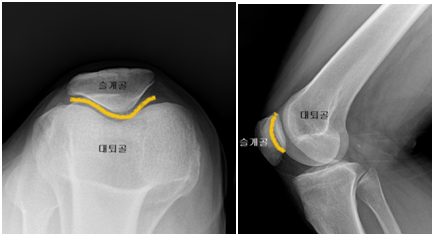

슬개대퇴 통증 증후군이란 무릎 앞쪽에 있는 뼈인 슬개골과 허벅지뼈인 대퇴골이 제대로 맞물리지 않아 발생하는 전방 슬관절 통증(슬개골 후방 통증)입니다. 진단을 내리기가 어렵고 애매모호하지만 전체 무릎관절 질환의 25% 이상을 차지할 만큼 흔한 질환이지요.

슬개대퇴 통증 증후군의 원인으로는 대퇴사두근 근력의 약화 또는 힘줄의 염증, 연골연화증이나 해부학적 모양의 이상 같은 슬개골 자체의 문제, 무릎 지방패드의 염증, 내측반월판의 병변 등 여러 가지가 있습니다. 저는 무릎을 굽히고 펼 때마다 슬개골이 바깥쪽으로 살짝 빠졌다 들어오는 슬개골 아탈구가 있습니다. 해부학적 구조는 괜찮은 것 같은데, 아마도 지나치게 운동을 안 해서 초래된 대퇴사두근 근력 부족에 의한 것으로 생각됩니다.